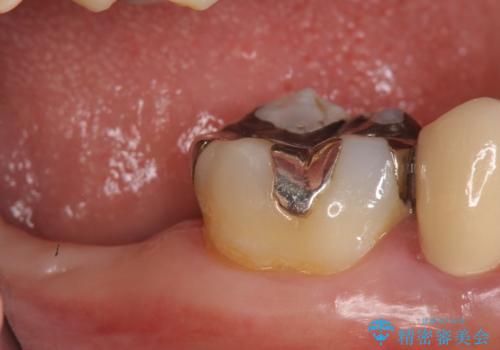

- 右下7番にインプラント治療を行った症例です。

CT撮影を行い状態を確認後、インプラント(ストローマン)の埋入(一次手術)を行いました。